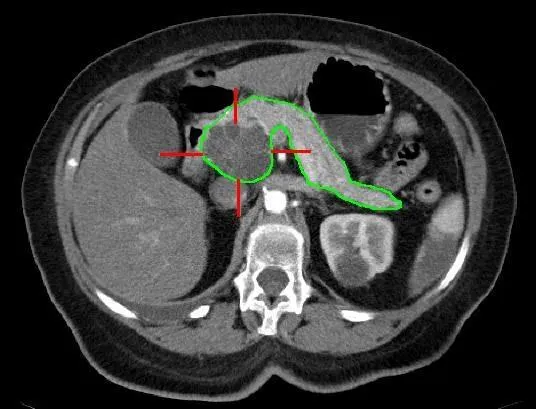

Cystic adenocarcinoma (marked in red) of the pancreas (outlined in green). Contrast‑enhanced computed tomography image.

MBq Disk Bew on Wikimedia Commons